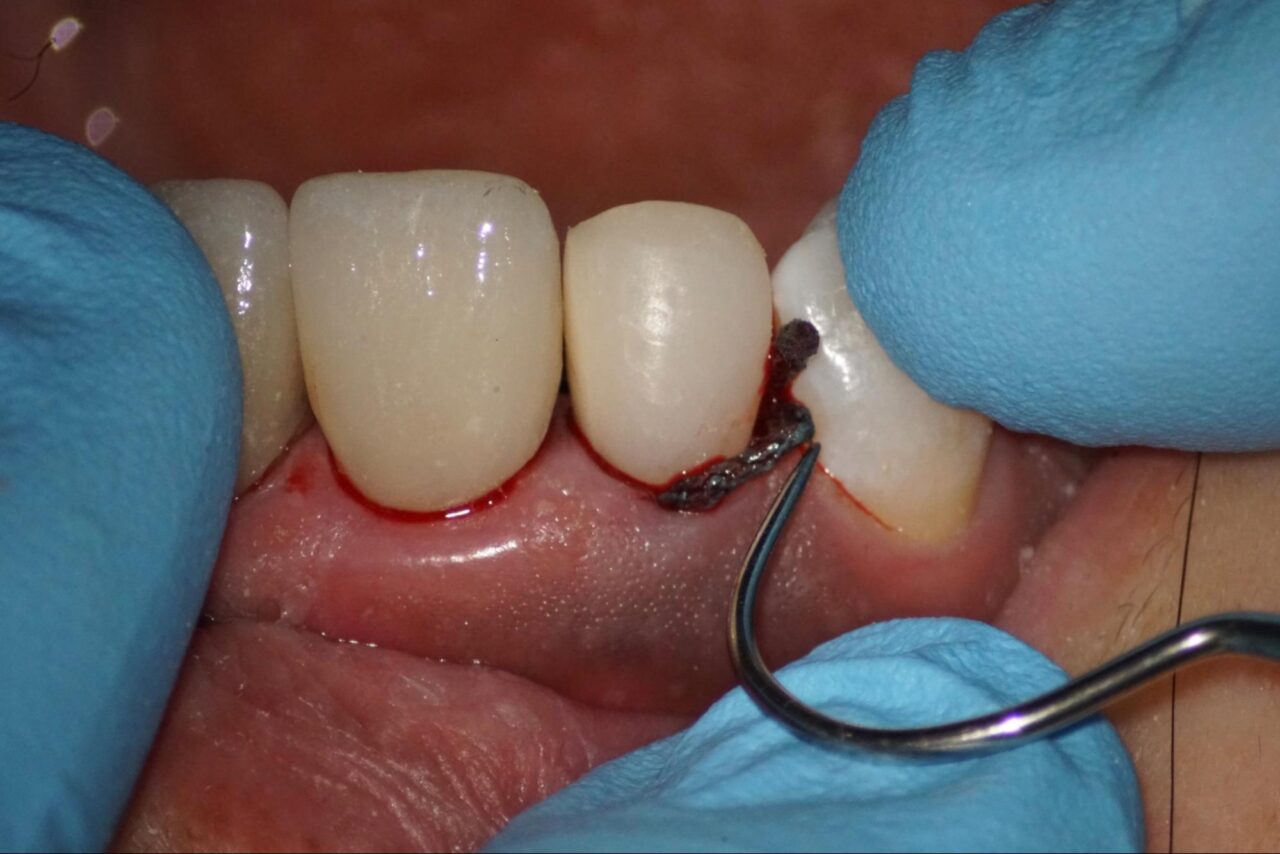

他院で歯根破折を疑われて、当院に来院されました。麻酔後にラバーダム防湿を行い、その後修復物を外します。

可能な限り健全歯質を削らないように細心の注意をはらって以前の修復物を外します。

感染部がグリーンに染まるカリエスディテクターを用いながら削っていくと頰側にクラックが入っている事が確認できます。

標準的な診断では、この時点で根管治療は終了となり、抜歯になりますが、吉松歯科医院では接着技術を用いて、可能な限り自分の歯を残すための治療を行なっています。